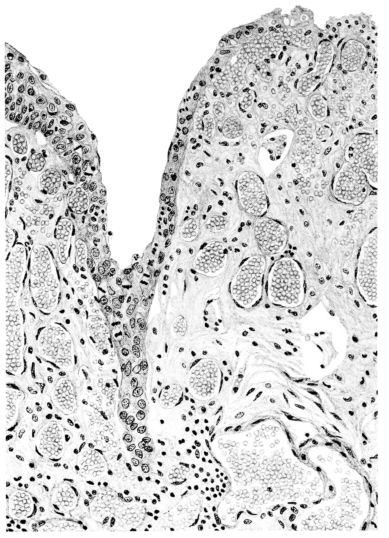

FIG. I. AUTOPSY NO. 99. ACUTE HEMORRHAGIC AND ULCERATIVE LARYNGOTRACHEITIS.

FIG. II. AUTOPSY NO. 98. DRAWING OF A SECTION THROUGH A TRACHEA SHOWING NECROTIZING HEMORRHAGIC INFLAMMATORY PROCESS OF THE MUCOSA.

FIG. III. AUTOPSY NO. 90. DRAWING FROM A LESION OF THE TRACHEA (SOMEWHAT OLDER THAN THAT ILLUSTRATED IN FIGURE II). THE MUCOSA IS ENTIRELY LACKING. CONGESTION AND EDEMA ARE THE STRIKING FEATURES IN THE SUBMUCOSA. THE NECROTIZING PROCESS HAS EXTENDED INTO THE MUCUS GLANDS. THIS IS SHOWN IN THE LOWER PICTURE.

FIG. IV. AUTOPSY NO. 205. CONGESTION AND EDEMA OF THE SUBMUCOSA AND REGENERATION OF THE TRACHEAL EPITHELIUM.

The changes are less marked, perhaps, in the trachea than in its finer ramifications. The mucosa is constantly more or less destroyed and large areas, usually focal, are entirely devoid of their epithelial covering. This is replaced by a sparse exudate, composed largely of red blood cells, mucus, a small amount of fibrin, and nuclear fragments (Fig. II). It may dip into the submucosa for a short distance, but usually these indentures are associated with the ducts of the mucous glands into which the inflammatory reaction extends. A more striking feature than the exudate, however, is the edema and the congestion of the submucosa. The loose areolar tissue of the submucosa is spread widely apart, and throughout it distended blood vessels are very conspicuous. Occasionally such a vessel is broken and actual hemorrhage appears in the submucosa. Occasionally, too, the inflammation extends down the duct to the mucous gland itself, and here, also, aplastic inflammatory reaction is evident, inasmuch as the acini now stain intensely red with the cells undifferentiated from each other and specked here and there by broken remains of the dead nuclei (Fig. III). After the disease has continued for a short period, even at the end of five or six days, some regeneration of the epithelial lining may be seen (3) (Fig. IV). But despite this, the acute picture persists, and there goes on, side by side, an attempted repair characterized by epithelial regeneration and the same evidence of acute change. Since the lesion is essentially a superficial one, scars or contractures of any extent are not encountered in the trachea, even in examples of the disease that have ended fatally only after many weeks.[4]